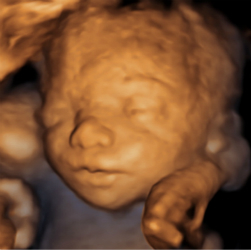

四维超声检查(动态三维超声检查)只是给宝宝拍了一张照片,对胎儿位置和姿势要求较高,胎儿孕周比较大才能拍的好,不能够评价胎儿的结构和发育情况。如果要求了解宝宝的结构是否正常,只需要选择系统产前超声检查。

点击这里看看四维彩超里的萌宝http://v.qq.com/page/u/8/9/u03089v9w89.html